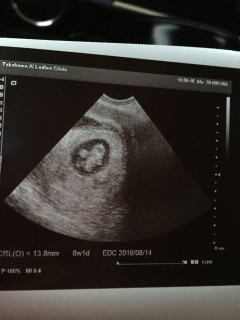

8w2dです。 赤ちゃんの大きさは13.8mm。 旦那さんと一緒にエコー拝見!かわいいクリオネちゃんがいました! 先生に赤ちゃん元気ですよーと言われ一安心。早く会いたいよー